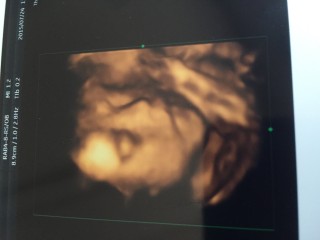

写真:24w4d:カナさん

男の子です!写真では手で顔を隠しててわからないけど、動画だと私似かな!?と(*^^*)800gくらいになったみたいで、どんどん大きくなってて嬉しいです♪